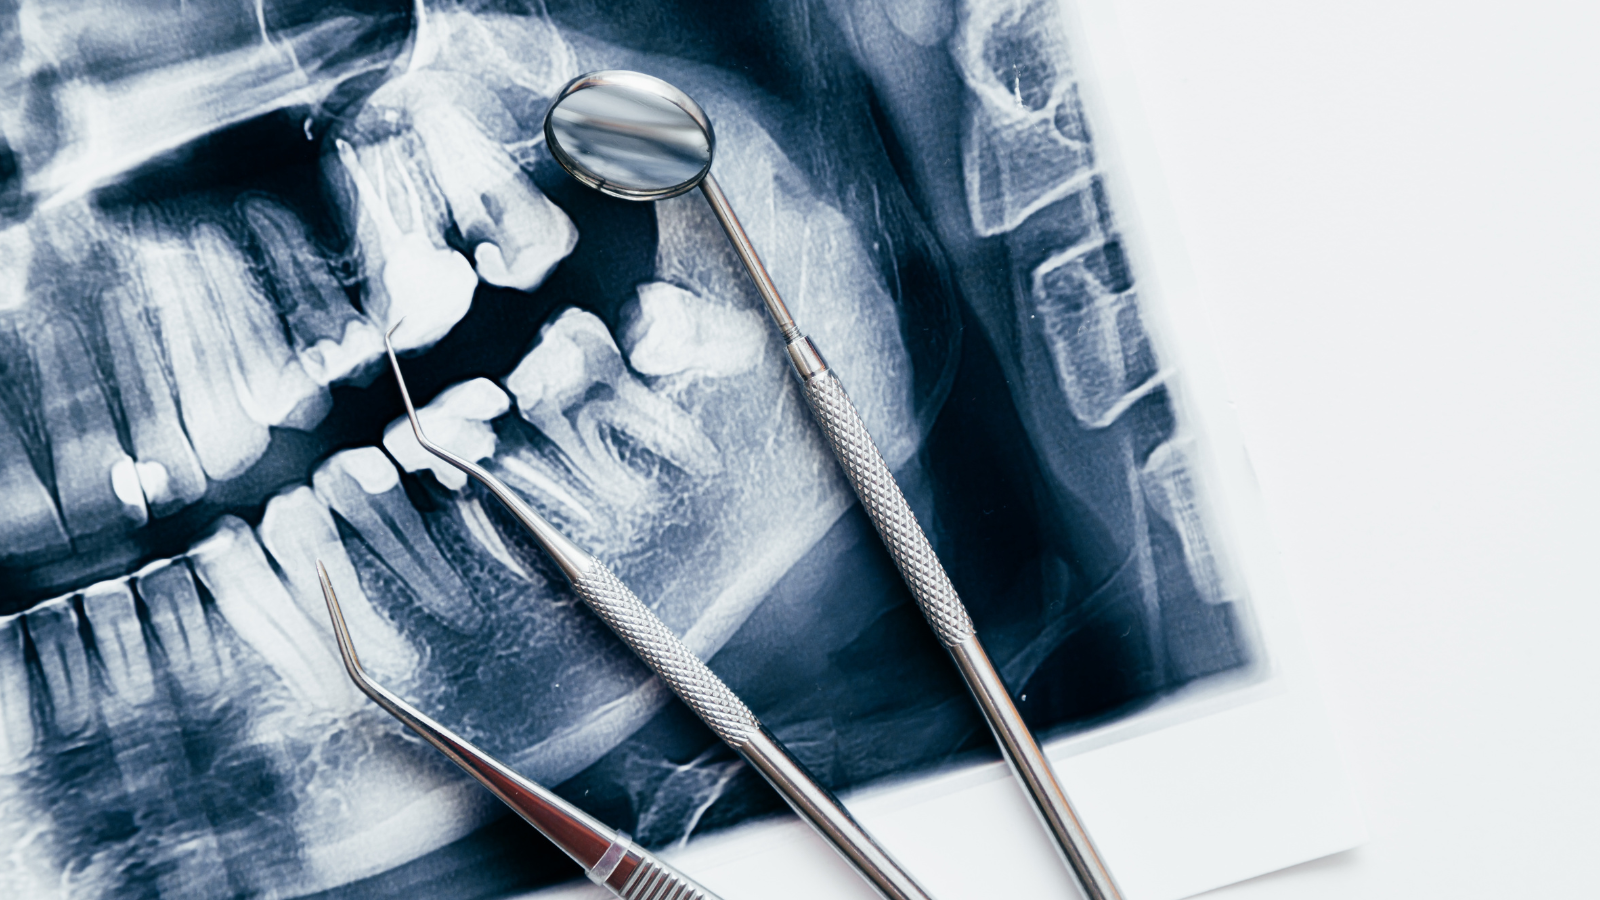

Răng số 7 là chiếc răng hàm lớn giữ vai trò chủ lực trong việc ăn nhai, nhưng cũng là chiếc răng có hệ thống ống tủy phức tạp và nằm sâu trong cung hàm. Chính vì độ khó kỹ thuật này, chi phí tham khảo trong điều trị tủy cho răng số 7 thường cao hơn các răng khác và có biên độ dao động khá lớn, từ 500.000 đến 5.000.000 VNĐ/răng.

- Mức độ phức tạp của hệ thống chân răng: Vì răng số 7 thường có từ 3 đến 4 ống tủy, thậm chí có những ống tủy cong hoặc bị canxi hóa đòi hỏi bác sĩ mất nhiều thời gian và công sức để làm sạch.

- Công nghệ áp dụng: Việc sử dụng các thiết bị tiên tiến như kính hiển vi nội nha hay máy định vị chóp sẽ có mức phí cao hơn so với phương pháp lấy tủy thủ công truyền thống.

Khác với răng cửa chỉ có 1 ống tủy thẳng, răng số 7 thường có từ 3 đến 4 ống tủy. Các ống tủy này thường nhỏ, hẹp và có thể cong bất thường. Việc tìm kiếm, làm sạch và tạo hình toàn bộ hệ thống ống tủy chằng chịt này là một quy trình tỉ mỉ, đòi hỏi sự chính xác tuyệt đối để không bỏ sót vi khuẩn.